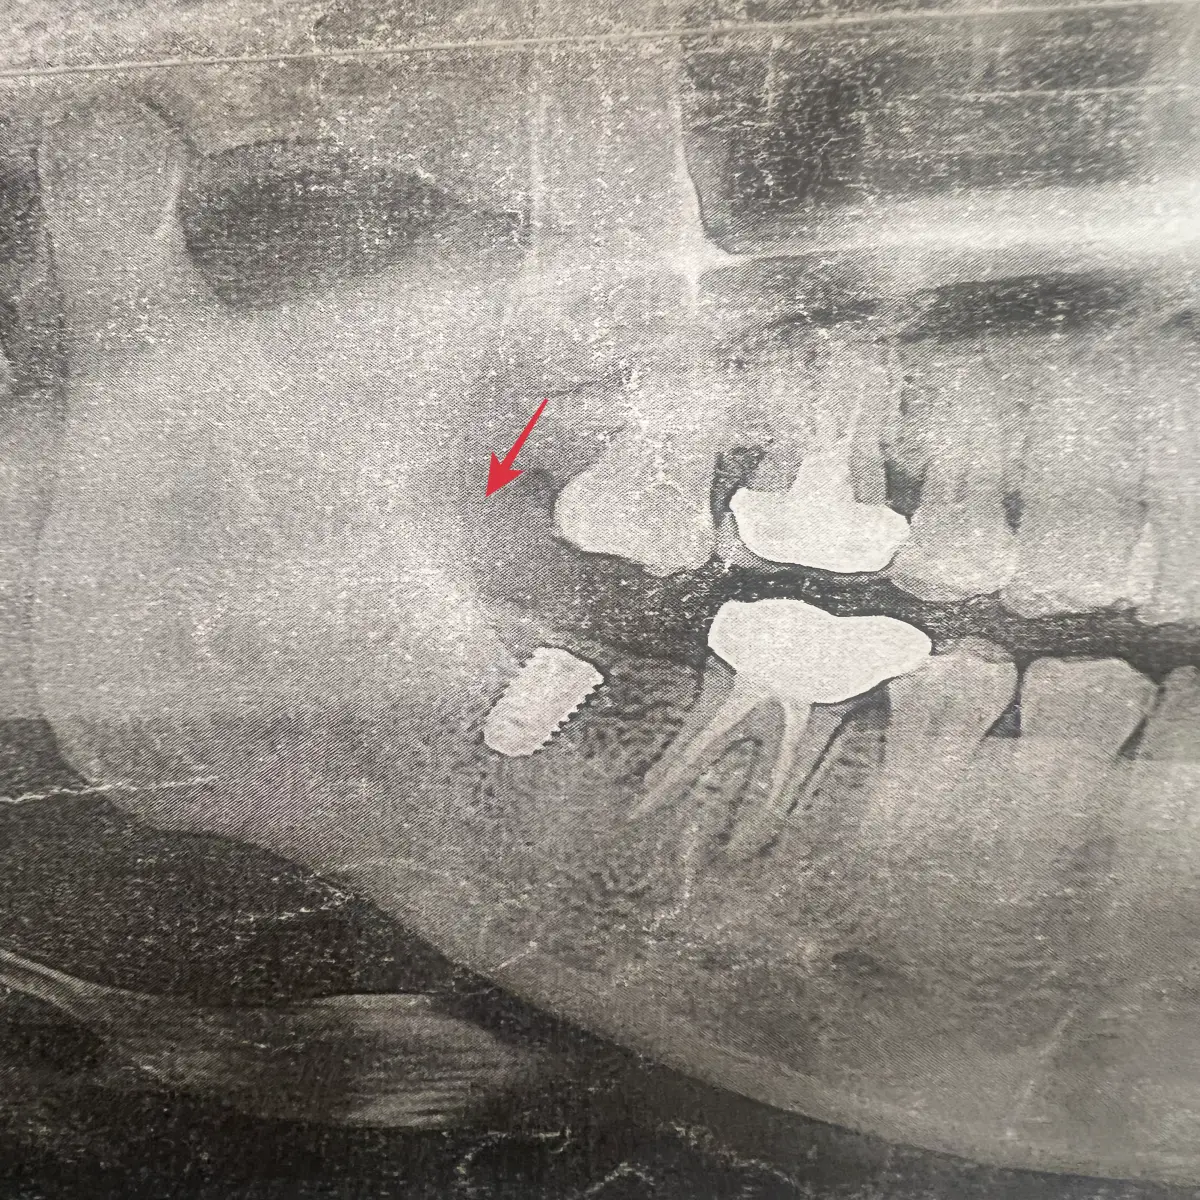

치과에서 3개월 뒤에 다시 오라고 한 이유는 잇몸뼈가 재생되는 기간이 3개월이기 때문인데요. 이후 임플란트를 심기 위해서입니다. 문제는 이 3개월이 지나고 시간이 지날수록 이 잇몸뼈가 다시 체내에 흡수된다는 점인데요. 제가 나름 젊어서 그런지, 운동을 열심히 해서 그런지, 모르겠다만, 치과에서 사진 찍고 잇몸뼈가 양호해서 정말 다행이라는 생각이 들었답니다.

정확히 말하면 이식 수술을 안 하면 임플란트를 미루는 거죠? 저는 운이 좋게도 잇몸뼈는 양호했지만 위 치아가 내려온 상황이었어요. 오른쪽 아래 어금니를 발치했는데 발치한 자리 위 치아가 내려왔습니다. 이렇게 되면 나중에 임플란트해도 치아 교합이 맞지 않아서 문제가 생기는데요.

제 치아 사진을 보시면 이해가 될 거에요. 처음 갔던 치과에서는 위 치아를 많이 깎아야 하는데 그러면 신경치료를 해야 하고 신경치료를 하면 치과 치아 보철물을 씌워야 된다고 하셨어요. 비용도 비싸고 신경치료가 또 아프잖아요. 순간 임플란트 미룬 걸 정말 후회했답니다. 결과적으로 어차피 해야 할 수술이라면 손해 보기 전에 이식 수술 후 임플란트를 하시는 것이 좋아요.